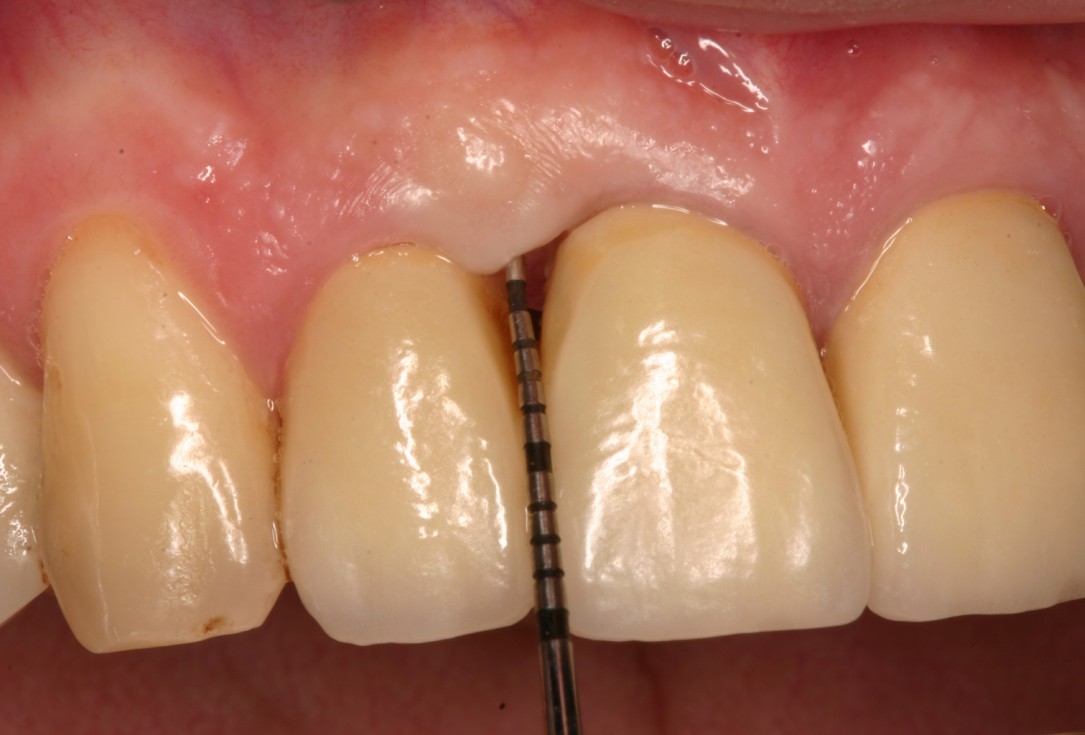

07/08 - Post-surgical probing (12 months) shows 3 mm PPD.Non-contained intrabony defect treated with the simplified papilla preservation flap in conjunction with Straumann® Emdogain® and a particulate bone grafting material - Prof. Dr. Dr. A. Kasaj